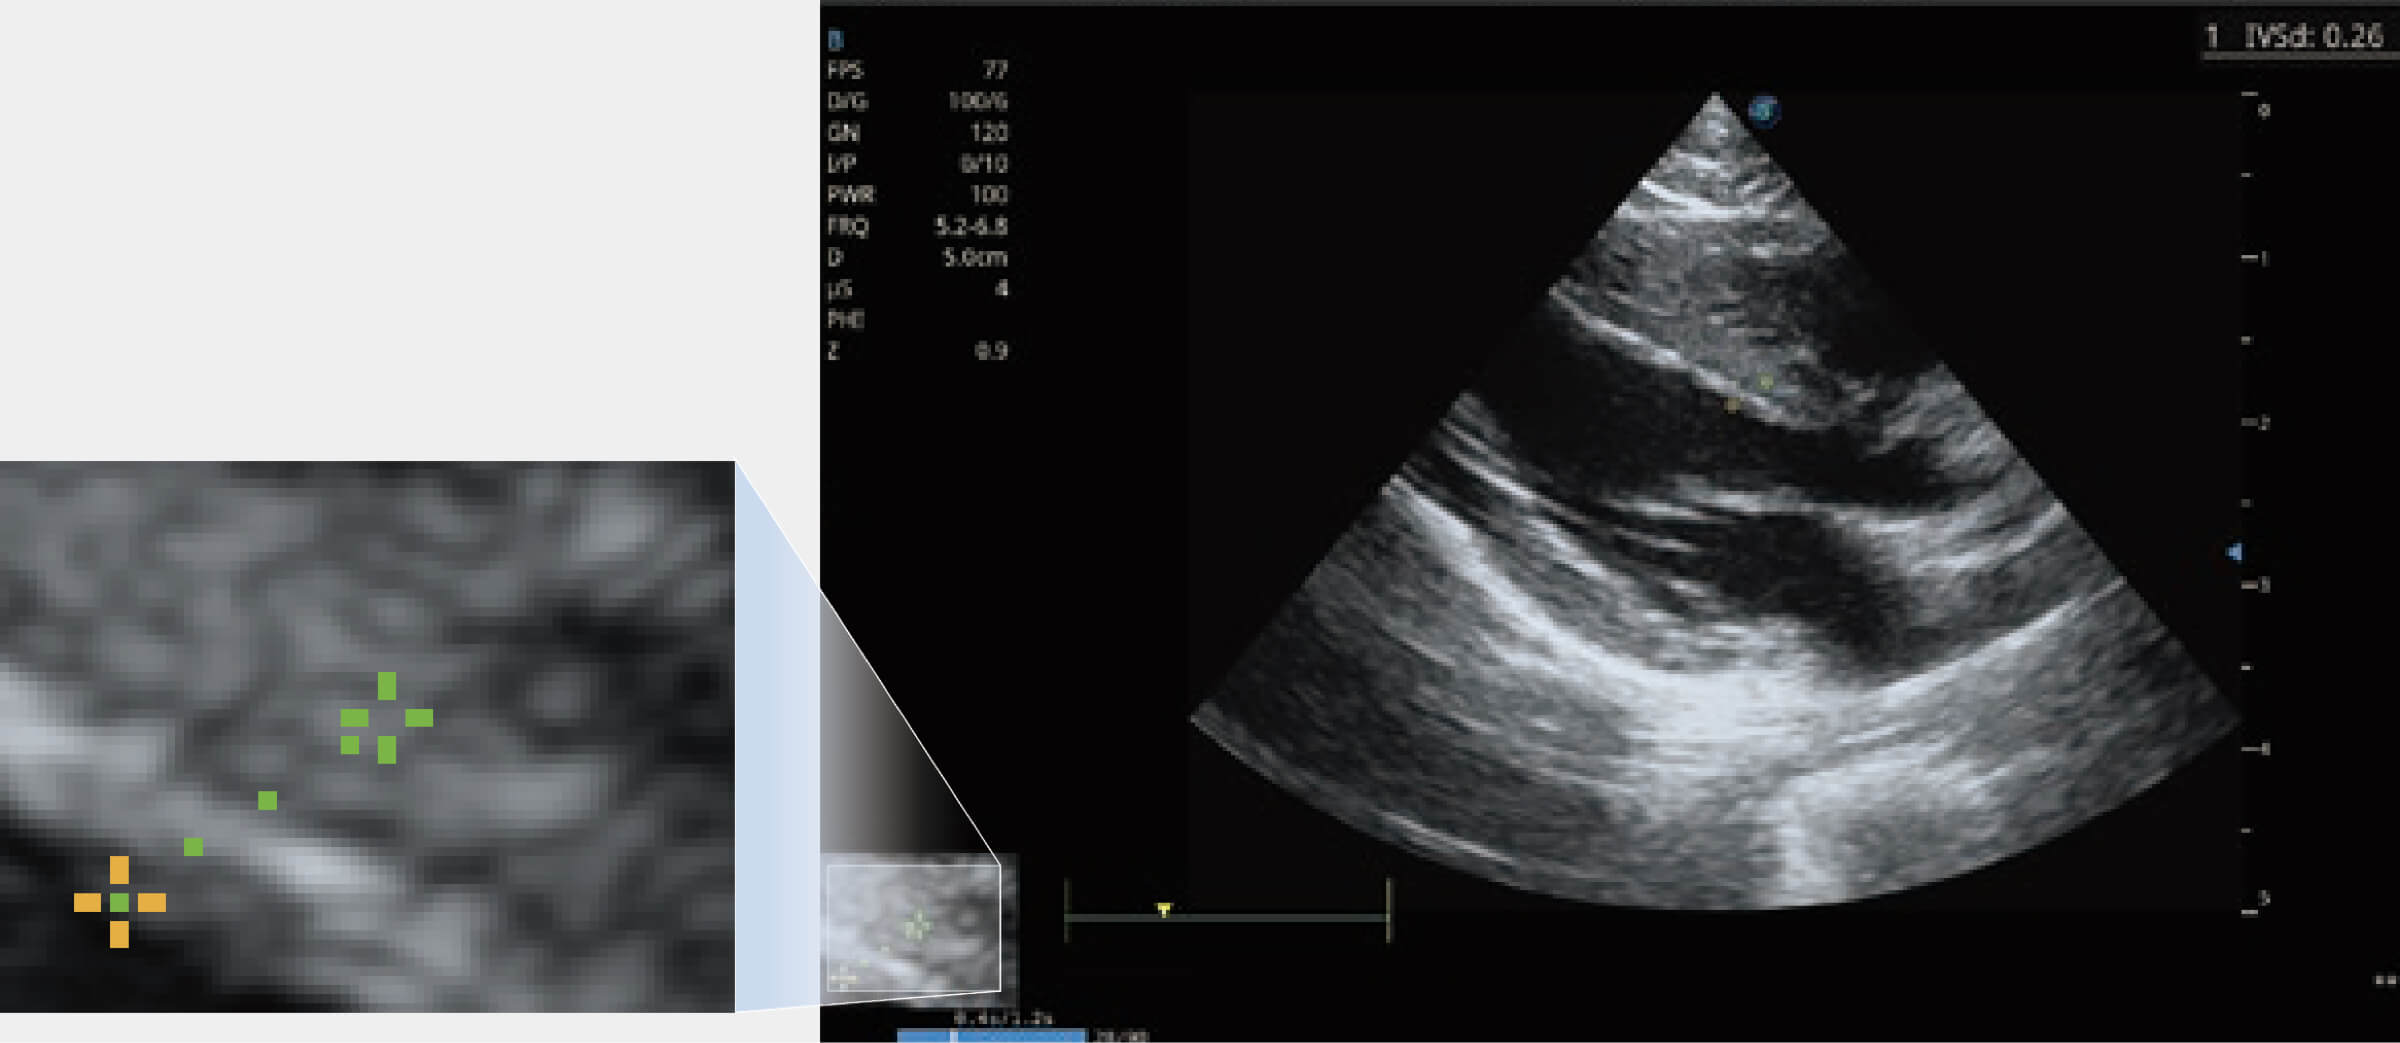

能夠基于左心室壁追蹤和辛普森法,自動(dòng)計(jì)算射血分?jǐn)?shù),支持多個(gè)可移動(dòng)點(diǎn)描跡,與手動(dòng)測(cè)量相比,極大節(jié)省了動(dòng)物醫(yī)生的時(shí)間和精力。